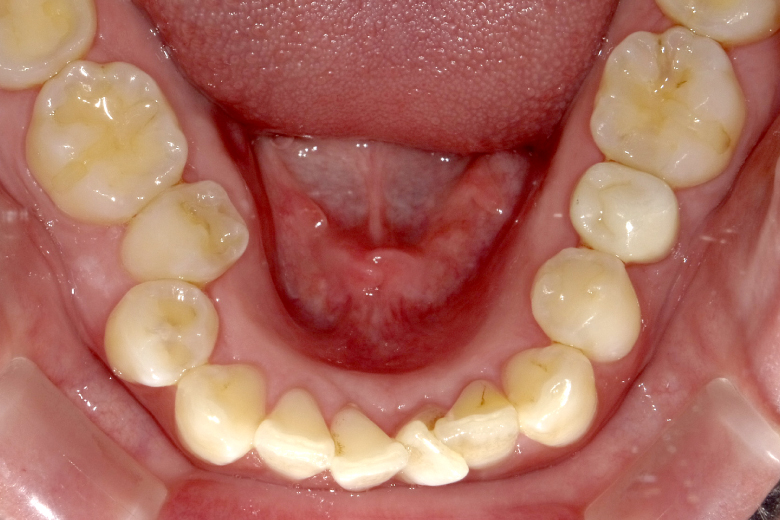

治療前

- 年齢・性別

- 29歳・女性

- 主訴

- 歯並びが気になる

- 診断

- 下顎の狭窄歯列弓(下顎がせまい)

- 叢生(そうせい / 歯並びがでこぼこ)

下顎の骨隆起が矯正装置の装着を妨げていたため、削合が必要と判断されました。

- 治療内容

- 両側の下顎隆起形成術(骨隆起を削合)後、バイヘリックスで下顎狭窄歯列弓を拡大(矯正装置で下顎を広げ)、マルチブラケット装着(矯正装置で歯並びを矯正)。

- 経過

- バイヘリックス・マルチブラケット装着にて矯正中(2021年1月現在)